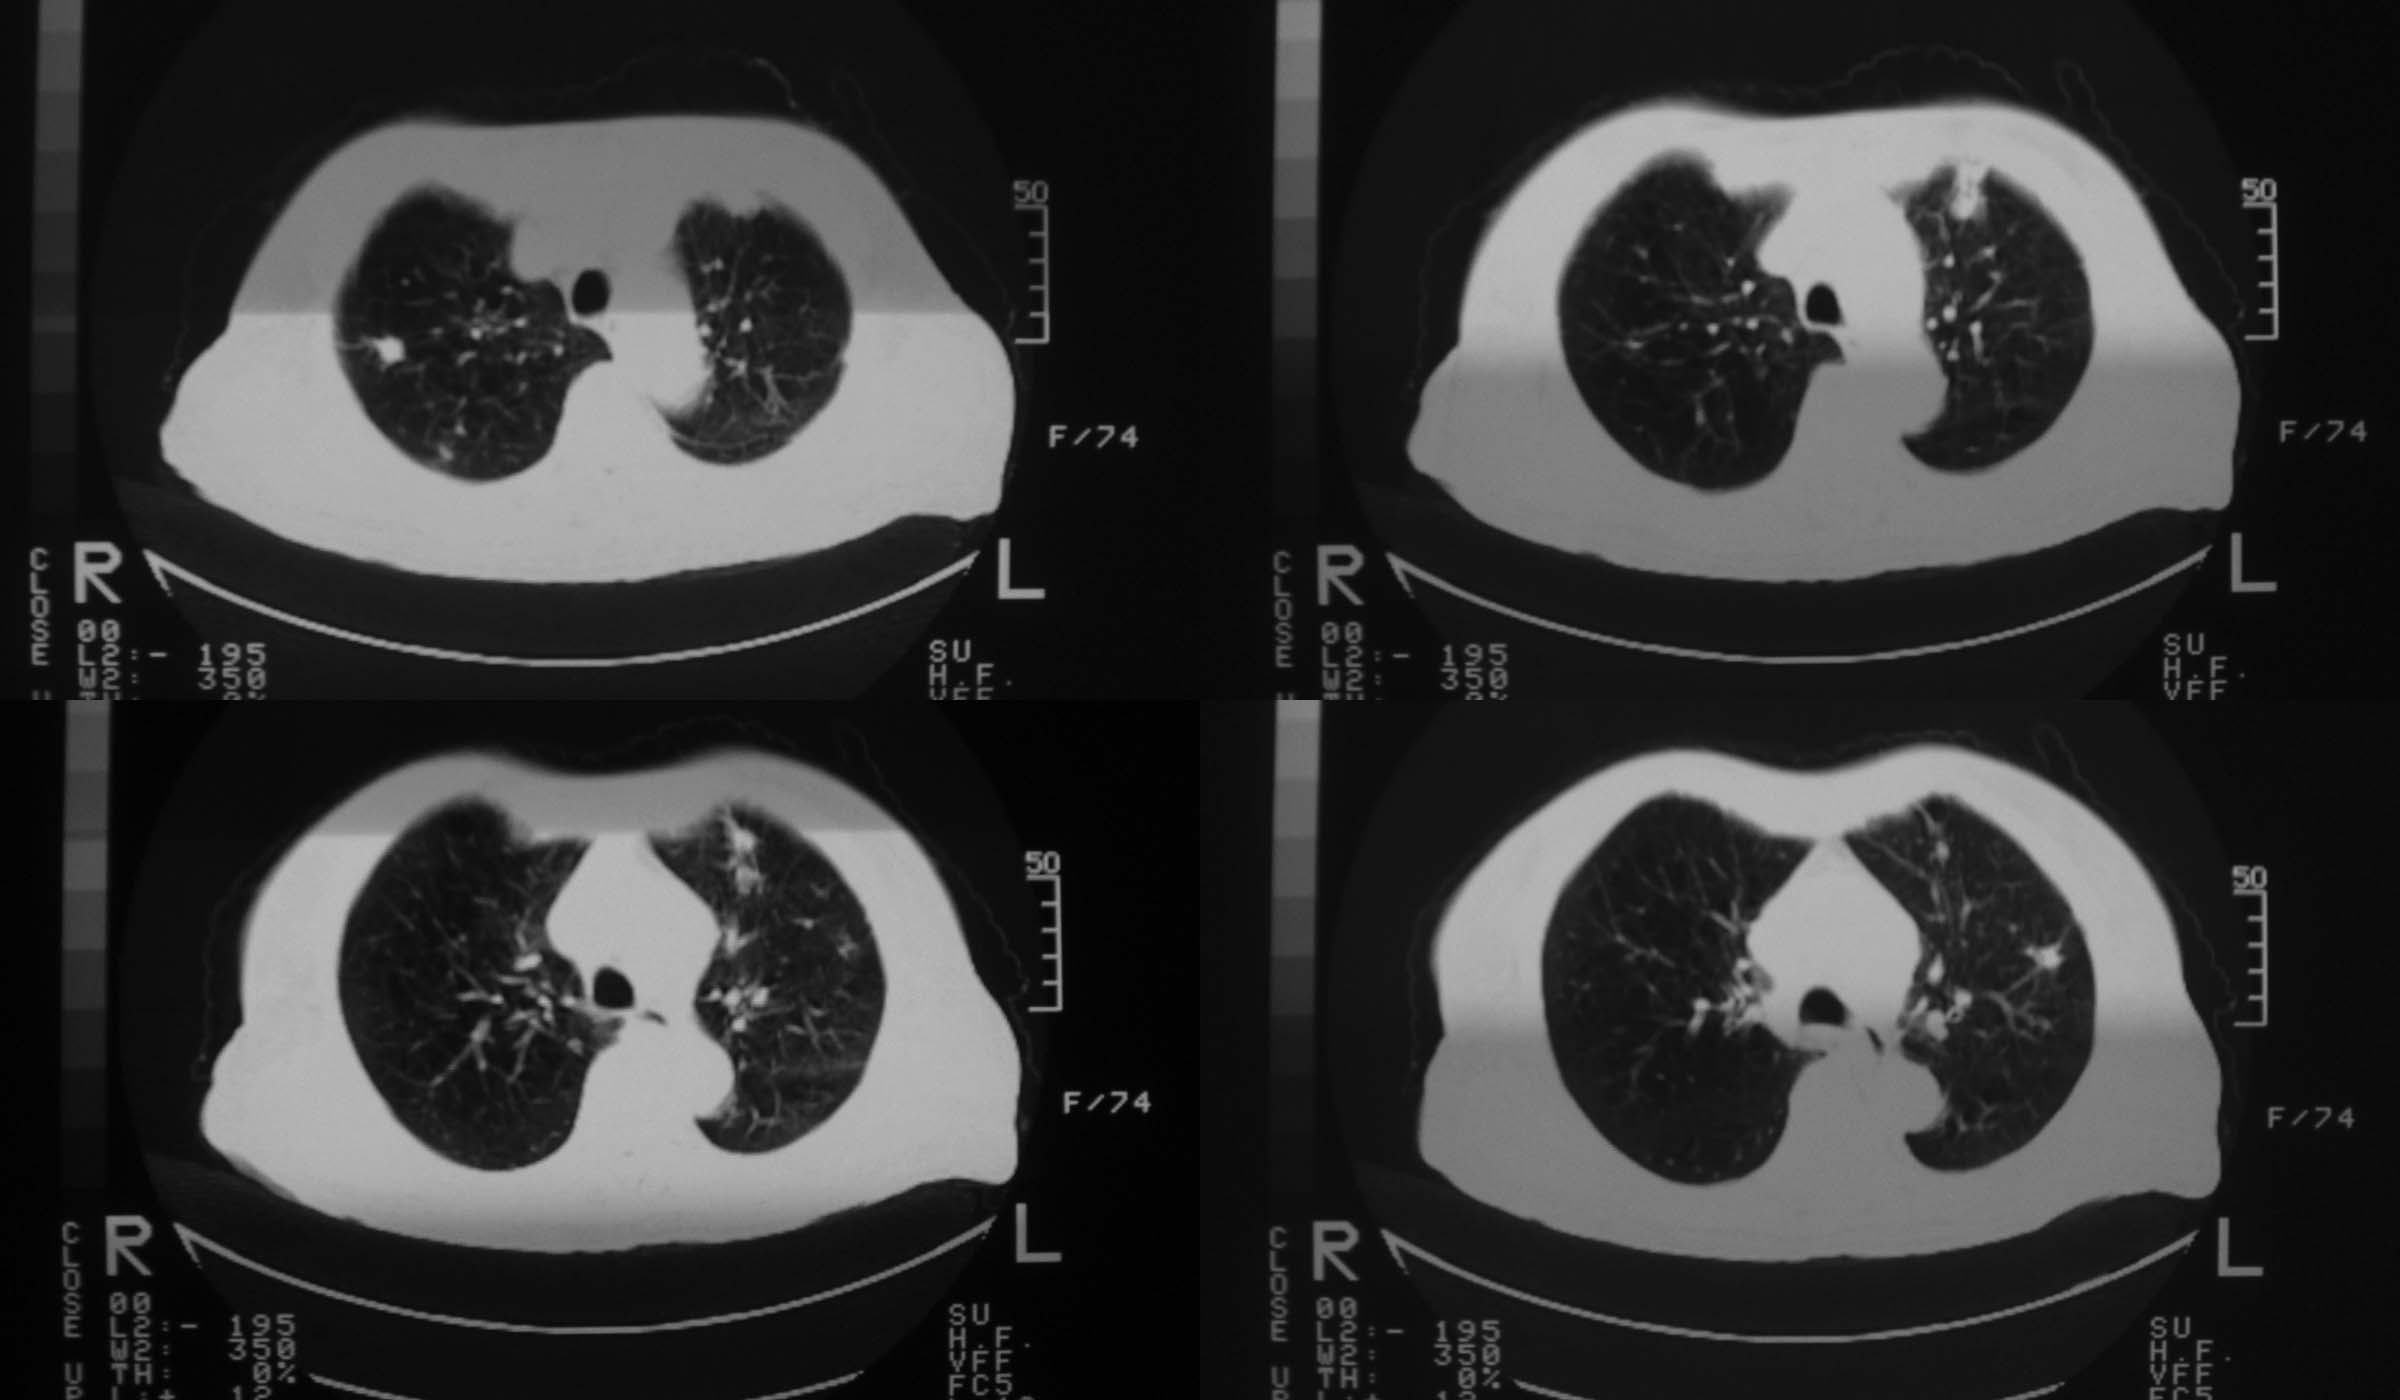

女73岁,咳嗽、胸痛。既往有结核病史20余年请各位老师看看是什么?结核?肺癌?

2008年1月7日

2008年2月29日

支持左下周围型肺癌(复查空洞缩小或消失已是肺癌的一个特点),双上肺继发型肺结核。

壁厚且不均匀空洞;右上叶尖段及左上叶尖后段多发结节影,部优可见钙化。支持肺癌并陈旧性肺结核。

二次复查见左下肺病灶增大,空洞缩小、消失,考虑左下肺癌,双上肺陈旧性肺结核。

陈旧结核应该存在,左肺病灶发展有点过快,不知病灶内部的ct值是多少?是否为液化的组织,不得而知。所以肺癌应该考虑但也应该打个问号。做个强化或穿刺吧。